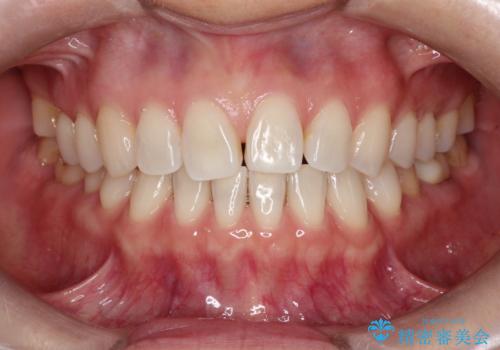

【インビザラインで再矯正】マウスピース矯正で隙間を閉じたい

- 過去に矯正を行ったあと、前歯の後戻りを主訴に来院されました。

マウスピース矯正にて隙間を閉じる計画をたて、治療を行いました。